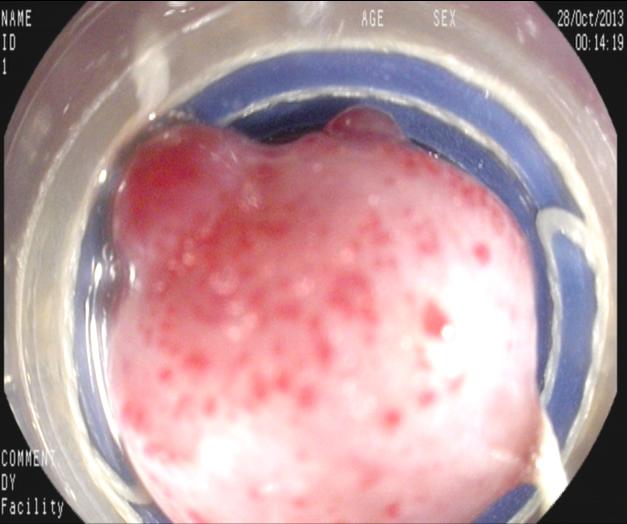

上2圖為重度曲張的食管靜脈,見(jiàn)紅色征較重。無(wú)活動(dòng)出血,顯然內(nèi)科止血治療有效。如果無(wú)積極有效的醫(yī)學(xué)干預(yù)再次出血率幾乎為100%,只是時(shí)間問(wèn)題,在受到食物磨擦,胃酸刺激、情緒波動(dòng)及自然病情變化等隨時(shí)有再出血可能,出現(xiàn)黑便甚至嘔血而危及生命,反復(fù)費(fèi)用也較高,再出血率也。